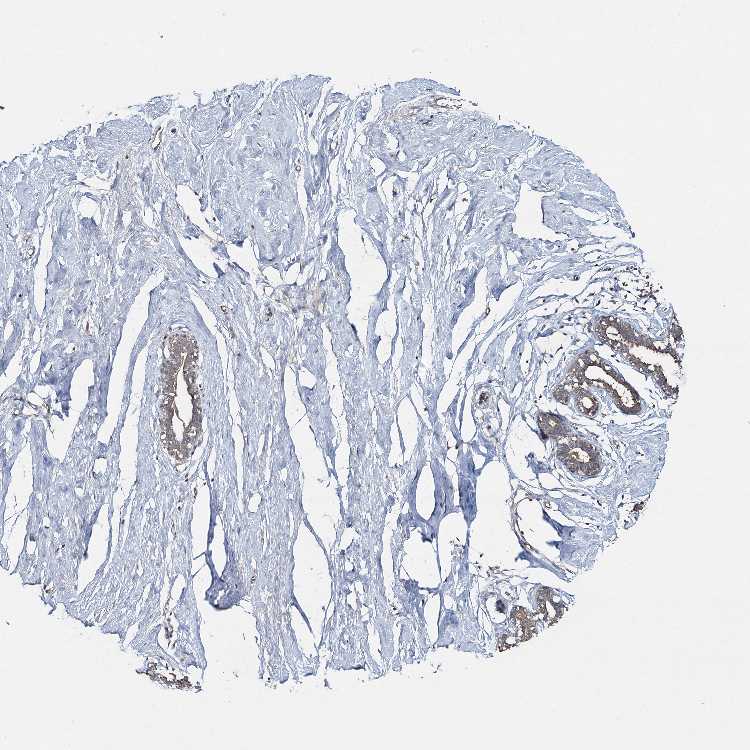

BREAST - Antibody stainingi

Antibody staining in the annotated cell types in the current human tissue is reported as not detected, low, medium, or high, based on conventional immunohistochemistry profiling in selected tissues. This score is based on the combination of the staining intensity and fraction of stained cells.

Each image is clickable and will lead to virtual microscopy that enables deeper exploration of all samples and also displays staining intensity scores, fraction scores and subcellular localization as well as patient and tissue information for each sample.

Antibody HPA039383

Adipocytes High

Glandular cells Medium

Myoepithelial cells Medium